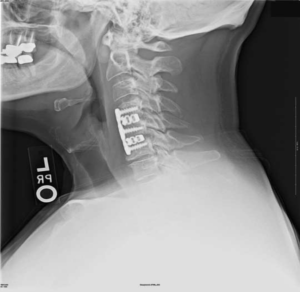

Для замещения удаленных позвонков у 8 (28%) больных применен сетчатый титановый протез «MASH» (рис. 1), который использовался нами с 2006 по 2010 г. Телескопическая система эндопротезирования, которая использовалась с 2010 по 2016 г., применена у 21 (72%) пациента (рис. 2). Спондилодез при помощи пластин выполнен у 19 (65,5%) больных, комбинированная стабилизация (титановые винты и пластины) — у 10 (34,5%) пациентов.

Рис. 2. Корпорэктомия позвонка СV с замещением дефекта раздвижным эндопротезом тела позвонка. а — интраоперационная фотография; б — послеоперационная рентгенограмма шейного отдела позвоночника.